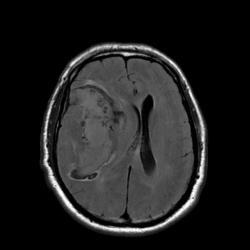

Наличие крови наиболее четко видно на T2* GRE импульсной последовательности.

Наличие крови наиболее четко видно на T2* GRE импульсной последовательности.

Гематому в данном случае с головой выдает периферическая полоска, окружающая образование с гипоинтенсивным (особенно на GRE ИП) МР сигналом. Иначе чем еще ее можно объяснить?

А гипоинтенсивная полоска - это проявления начинающегося распада гемоглобина (метгемоглобин).

В данном случае это классический геморрагический инсульт. По моему опыту с таким смещением срединных структур как на представленных МР-томограммах нейрохируги редко берут на операцию - благополучный постоперационный прогноз маловероятен, да и большиноство пациентов погибают за считанные часы, многие на операционном столе. Евгений, наверное, узнает у пат.анатомов результат вскрытия и напишет нам уже верифицированный диагноз.

Работая совместно с нейрохирургами, которые занимаются сосудистой патологией, перед нами постоянно ставят именно эту задачу: определить причину кровоизлияния, а отсюда и тактику доступа при нейрохирургическом вмешательстве (пункционно идти на ту или иную гематому или открытым доступом или вообще не вмешиваться и вести определенных больных консервативно). Вы правы, что при таком обширном кровоизлиянии МР-ангиография (особенно на 2-3 сутки после начала заболевания) часто оказывается бесполезной, так как из-за зоны кровоизлияния определенная часть сосудов основания мозга просто не визуализируется, или значительно смещена и деформирована именно зона интереса, что увеличивает риск неправильной трактовки данной патологии. Тогда нейрохирургам приходится применять классическую селективную ангиографию (если они действительно подозревают аневризму). Но в данном случае мы видим МР-томограммы и МР-ангиограммы в первые часы гемор.инсульта, поэтому сосуды хорошо получились. А МР-трактография (у нас нет такого оборудования как у Евгения, поэтому мы эту методику не применяем) может тоже помочь планировать операционный доступ и объем оперативного удаления гематомы с учетом видения расположения проводящих путей, их заинтересованности в патологическом процессе с целью минимальных послеоперационных осложнений и неврологического дефицита. Эта методика сейчас актуальна не только для изучения опухолей но и сосудистых заболеваний. С уважением Visus 07